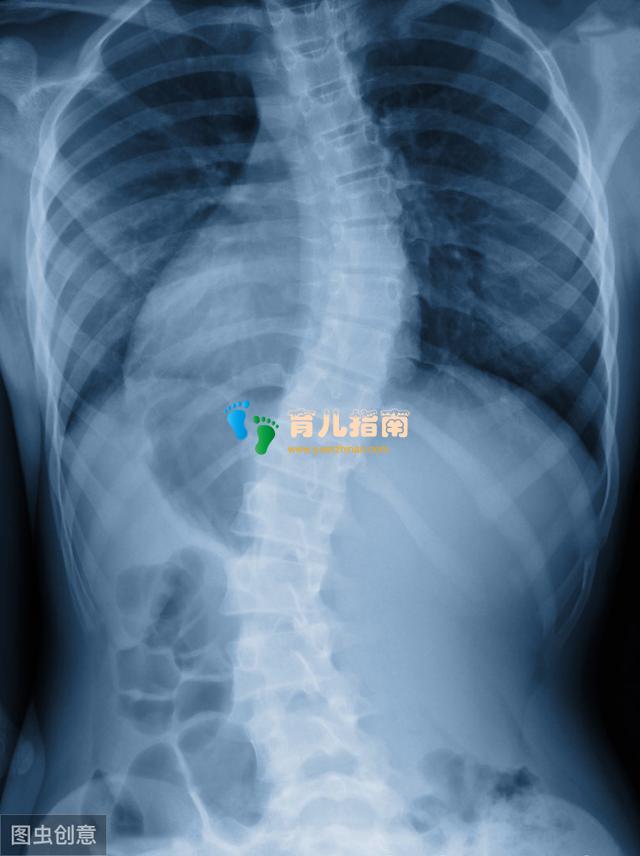

而上文家长关心的脊柱侧弯问题,我也要讲一下,首先要讲一下脊柱侧弯是什么,简单说脊柱侧弯是指脊柱发生弯曲,是一种脊柱结构性的侧弯,原因有很多,有的是先天性的也有后天形成的,临床上女孩比男孩多见。一般发生在初中或高中的孩子身上的脊柱侧弯考虑特发性脊柱侧弯,意思是原因不明确,典型症状是双肩高低不平,脊柱偏离中线,肩胛骨一高一低,一侧胸部出现皱褶皮纹,前弯时双侧背部不对称。当孩子一侧肩胛似乎比另一侧高时,或衣服不能拉直时要首先怀疑到有脊柱侧弯,但更多的是在体格检查中查出的,最早的表现可能是久坐或站后出现腰部无力等。脊柱侧弯10度及以上就需要到医院专业的骨科医生那里就诊,根据发现时的年龄和弯曲的程度或类型,治疗可分为观察、支具矫正或手术治疗。